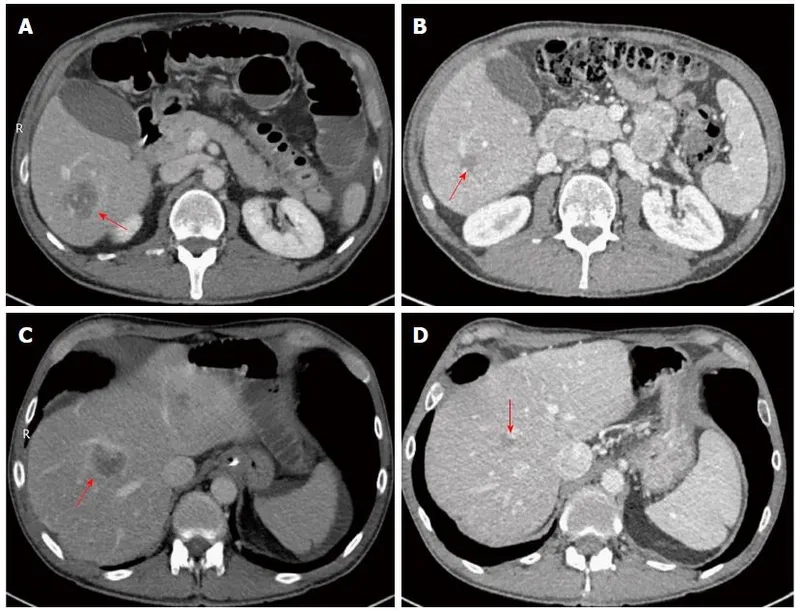

Image of the disease Alpha-1 Antitrypsin Deficiency